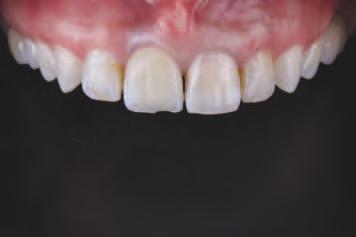

O pac entă de 61 an s-a prezentat la Per odont cs/Per odontal Prosthes s Cl n c d n cadrul Un vers ty of Pennsylvan a School of Dental Med cne dor nd în pr nc pal să a bă „d nț f xaț ” în locul protezelor mob le ex stente (f g. 1). După f nal zarea unu examen stomatolog c cupr nzător, nclus v exam narea extra- ș ntraorală, evaluarea pr n tomograf e computer zată cu fasc cul con c (CBCT), fotograf erea dentară ș întocm rea f șelor dentare, s-a creat un plan pentru real zarea une reab l tăr full-mouth folos nd mplantur ș proteze dentare f xe. Pac enta purta proteze totale moble retenț onate pe m n - mplantur atât la mand bulă, cât ș la max lar. În t mpul evaluăr n ț ale, ea ș -a expr mat preocupăr le legate de estet ca restaurăr lor ex stente în ceea ce pr vește expunerea g ng vală ș

2. Pacienta prezenta expunerea excesivă a componentei gingivale din protezele existente.

3. Situația pretratament mandibulară edentată cu cele patru mini-implanturi existente.

⊲ COMPLETE DIGITAL WORKFLOW CASE STUDY

Proiectarea și fabricarea digitală a restaurărilor CAD/CAM într-un

caz estetic complex

Un ob ect v pr nc pal al restaurăr lor dentare este să m te d nț natural în armon e cu fața nd v dulu . S-a demonstrat de mult t mp că un zâmbet atrăgător are un mpact semn f cat v asupra percepț e ș a d scernământulu celorlalț . De-a lungul an lor, în stomatolog a estet că s-au făcut progrese substanț ale, în spec al în ceea ce pr vește avansarea tehnolog lor d g tale care fac l tează pro ectarea

tr d mens onală (3D) a zâmbetulu , personal zată, în armon e cu fața pac entulu . Deoarece percepț a estet c dentofac ale este determnată ș de prefer nțele personale ș de factor cultural , este esenț ală ntegrarea pac entulu în procesul dec z onal pentru a at nge ob ectvele opt me de tratament estet c. În ult mele decen , pro ectarea zâmbetulu s-a mutat progres v de la fluxur de lucru analog ce la d g ta-

le, care s-au dezvoltat ulter or de la nstrumentele b d mens onale (2D) la cele tr d mens onale (3D). Implementarea nstrumentelor d g tale ș a nteracț un onl ne a îmbunătăț t comun carea între cl n c en , tehnc en dentar ș pac enț . Îmb narea fotograf lor 2D cu f ș erele d g tale 3D perm te tranz ț a către un flux de lucru complet d g tal ș fac l tează pro ectarea d g tală a zâmbetulu gh dată fac al. Instrumentele no de

pro ectare d g tală a zâmbetulu pot f folos te pentru a contura ș mod f ca d g tal zâmbetele pac enț lor dar ș pentru a v zual za rezultatul îna nte de pract carea unor procedur revers b le. De asemenea, astfel de nstrumente perm t anal za met culoasă a caracter st c lor fac ale ș dentare ale pac entulu pentru a fac l ta pro ectarea d g tală. În mod ob șnu t, un f ș er STL al pro ectăr d g tale a zâmbetulu este mpr mat în 3D, ar acest model este folos t pentru producerea une s mulăr în scaunul stomatolog c. Ver f carea tuturor parametr lor estet c este esenț ală, deoarece aceeaș pro ectare 3D a zâmbetulu sau o mod f care corespunzătoare a aceste a este ut l zată pentru fabr carea restaurăr lor def n t ve. De fapt, toț paș ulter or , nclus v t pul de tratament restaurator, mater alul ș pro ectarea preparaț e dep nd d rect de prec z a aceste pro ectăr n ț ale.